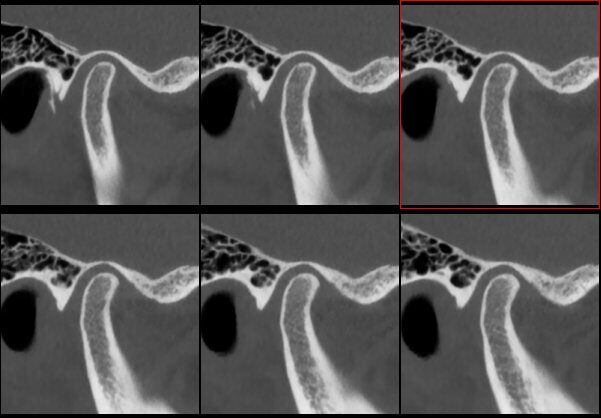

ATM Bocca Aperta